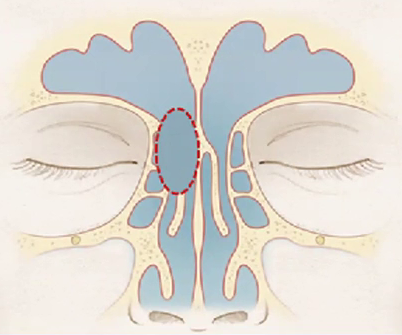

Cite os limites do recesso do seio frontal:

• Anterior = Frontal beak (e Agger Nasi).

• Posterior = Bula etmoidal

• Medial = Porção vertical da concha média

• Lateral = Lâmina Papirácea